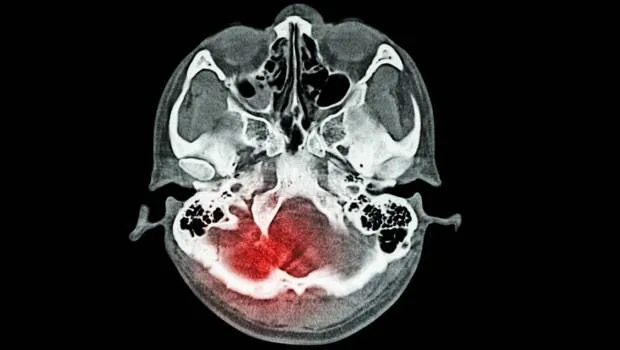

Medipol Üniversitesi Hastanesi Fizik Tedavi ve Rehabilitasyon/Algoloji Uzmanı Doç. Dr. Engin Çakar, inmenin ölüm sıralamasında üçüncü en büyük risk olduğunu, yetişkin sakatlıklarında da başlıca sebeplerden olduğunu ancak sağlıklı yaşayarak felcin önlenebileceğini ifade ediyor. GENETİK YATKINLIK Önemli bir risk faktörü. Ailenizde inme riski varsa kişinin kendisinde de bu risk artmış demektir. Geçici beyin damar tıkanıklığı iyi tanınmalı. Eğer hastada kısmi felci taklit eden, 24 saatten kısa süren bir atak geçirmişse, bu hasta yüksek ihtimalle normal kişiye göre, on kat daha yüksek bir riskledir, tedbir alınmadığı takdirde 5 yıl içerisinde bir inme geçirecektir. Bu durumda hızlıca sağlık kuruluşuna başvurmalı, tedbir alınmalı. YAŞ 65 yaş üstünde sık görülür ancak hastaların %30’u genç hastalardır. Bu yüzden her yaşta tedbir almakla yükümlüyüz. Genç yaşta erkeklerde, ileri yaşlarda da kadınlarda daha sık görülüyor. İnme, yaşlı kadınların ölüm sebeplerinde meme kanserine yakın bir risk faktörüdür. Ayrıca genç yaştaki kadınlarda doğum kontrol hapları ve menopoz sonrası kullanılan hormon ilaçları da riski artırabiliyor. İNMEDEN KORUNMAK İÇİN BUNLARA DİKKAT - Eğer genetik olarak ailenizde bu risk varsa ve yüksek tansiyon, kalp ve şeker hastalığı varsa sağlık kuruluşuna başvurulmalı. - Bir Fizik Tedavi veya nöroloji hekimine başvurduğunuzda ailede inme riski varsa, bu durum özellikle belirtilmeli. - Engellenebilir en büyük risklerden birisi tansiyon yüksekliğidir. Bu yüzden hastalığın takibi iyi yapılmalı. Fiziksel aktivite ve beslenme alışkanlıklarını düzeltilmeli ve gerekirse tansiyon düzenleyici ilaç kullanarak tansiyon düzeltilmeli. - Kalp hastalıklarında özellikle koroner kalp damar hastalıkları ve ritim bozuklukları çok önemli. Bunlar kontrol altına alınırsa damarlarda sertleşme ve pıhtılaşmayı engelleyerek riski ortadan kaldırılabilir. - Kolesterolde yağlı beslenme ve hareketsizlik bu durumu artırıyor. Damar sertliği ve damarlarda tıkanıklığa sebep oluyor. Yeme alışkanlıklarımızı ve fiziksel aktivitemizi artırarak bunu engelleyebiliriz. - Uyku apnesi beyne kan gitmesini azalttığı için felce sebep olabiliyor. Bu yüzden apneyle ilgili tedbirlerin alınması gerekiyor. - Eğer bir şeker hastasıysanız normal bir insana göre 2-4 kat felç geçirme riskiniz yüksektir. Özellikle genç yaşta olanla kilo alımına dikkat edilmeli ve fiziksel olarak aktif olmalı. - Dolaşım problemleri de inmeye sebep olabiliyor. Kalp damar hastalıkları dahil tüm damarsal hastalıklar inme riskini artırıyor. SAĞLIKLI BİR YAŞAM İÇİN NELER YAPILMALI? - Sigaradan tamamen uzak durun. Sigara, damarlardan pıhtı oluşmasını hızlandırıyor. Kanın akışkanlığını azaltıyor ve damar sertliğinin oluşmasını hızlandırıyor. - Ne yediğinizi kontrol ederek yaşayın. Beslenmenizi düzenli hale getirin. Meyve sebze ağırlıklı ve lif zengini yiyecekler tüketin. - Tuzu hayatınızda mümkün olduğunca kısıtlayın. - Kolesterol ve vücutta yağ yapıcı yiyeceklerden, özellikle sentetik ve trans yağları hayatınızdan çıkarın. - Sağlıklı kiloyu koruyun. - Aktif yaşamı korumak lazım. Fiziksel aktivite vücut için koruyucudur. Çünkü fiziksel aktivite kilo kaybına, stresin azalmasına, tansiyonun düşmesine, kolesterolün azalmasına, şekerin düzelmesine katkı sağlar. Günde en az 30 dakika aktif spor yapmak gerekiyor. Bu yüzden sağlıklı yaşam için her gün 10.000 adım diyoruz. - Aşırı alkol de inme riskini artırıyor. Bunu da en çok tansiyon yüksekliğine sebep olarak inme riskinin artmasına sebep oluyor. http://www.hurriyet.com.tr/inmeden-korunmak-icin-neler-yapmalisiniz-40060393